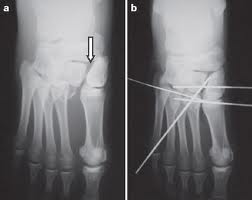

A articulação de Lisfranc é formada pelas bases dos cinco metatarsianos, com os três cuneiformes e com o cubóide. A base do segundo metatarsiano é o ponto-chave da estabilização dessa articulação, pois a mesma está encaixada no tarso e somente haverá luxação completa se essa articulação for rompida ou fraturada.

A conexão ligamentar entre a base do primeiro e do segundo metatarsiano é formada pelo ligamento também denominado de Lisfranc, que constitui um dos principais estabilizadores dessa articulação, além dos tecidos moles, tendões, fáscias e musculatura intrínseca da região.

O desvio da fratura-luxação das bases dos metatarsianos pode ser dorsal, plantar, medial, lateral ou até mesmo combinado. O desvio dorsal é o mais comum, associado a um mecanismo de lesão indireto, devido a abdução forçada do antepé, isolada ou em combinação, contrapondo-se ao mecanismo de lesão direto, decorrente de queda de um objeto sobre o calcâneo quando este se encontra em flexão plantar forçada.